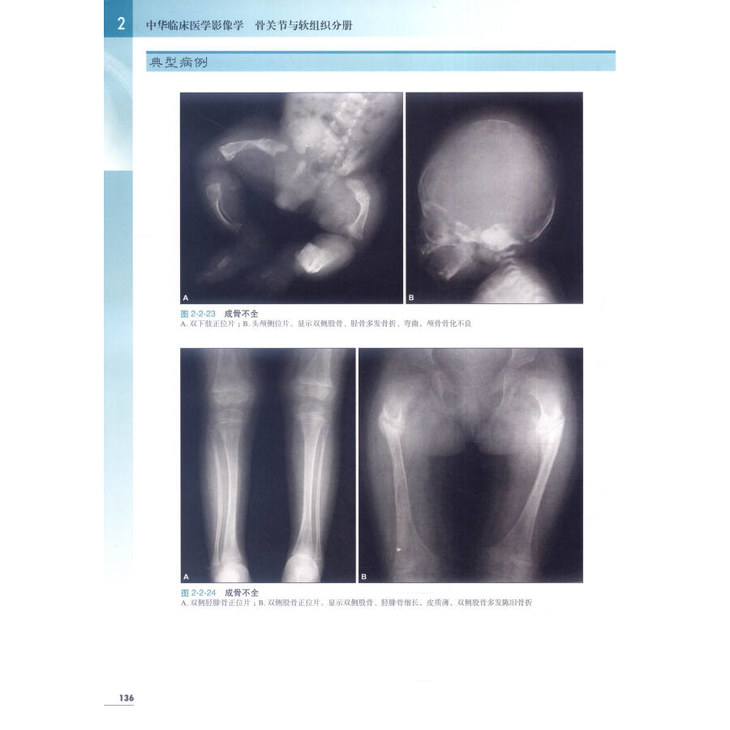

★ 内页插图 ★